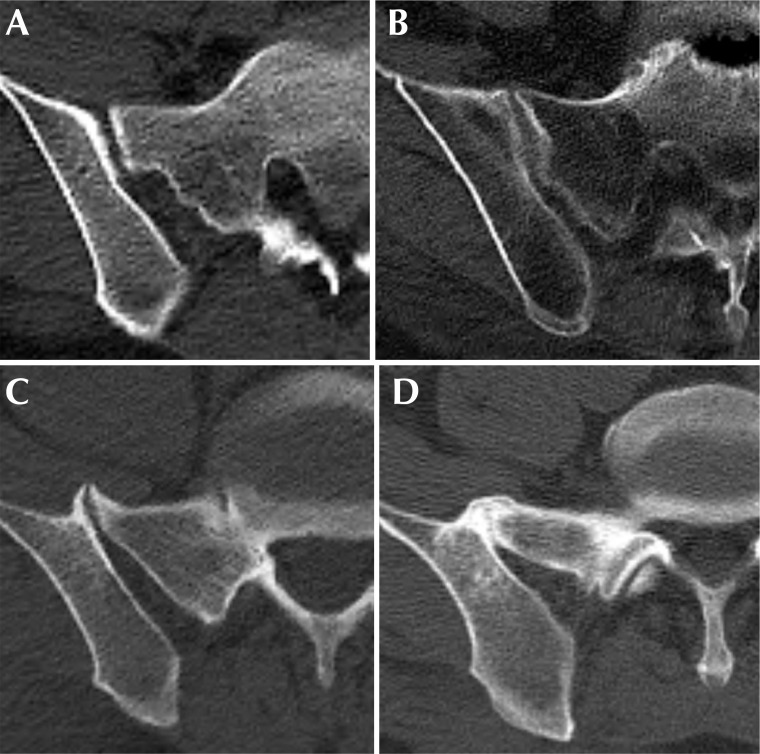

Materials and methods: A retrospective analysis was conducted on 272 patients diagnosed with pelvic ring injuries between January 2004 and October 2023. Patients were categorized into non-ankylosed (n=185) and ankylosed (n=87) SIJ cohorts. The prevalence of SIJ ankylosis in our study sample was 32.0% (87/272). Patient demographics, SIJ ankylosis, PL, and fracture classification using computed tomography were compared between the two groups. PL was defined as any type of posterior ring injury with fracture lines extending to the region posterior to the iliac pillar, with or without SIJ subluxation or dislocation. To determine the association between SIJ ankylosis and PL, a logistic regression analysis adjusted for age, body mass index, sex, and energy of injury mechanism was performed.

Abstract Image